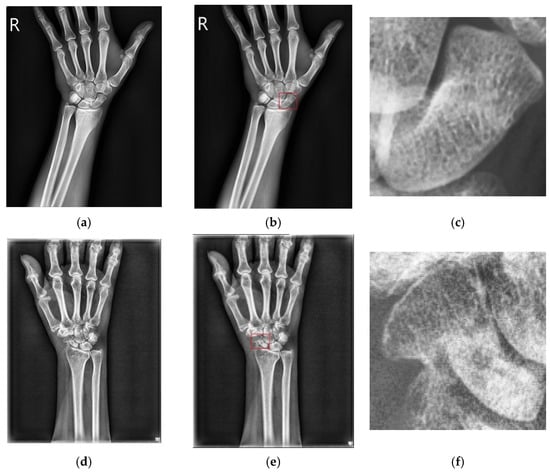

2.2.1. Scaphoid Area Detection

2.2.2. Fracture Area Detection